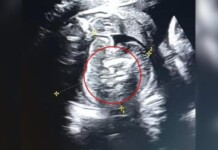

Bebê nasce com dois fetos dentro do abdômen em caso raro da medicina

Uma mulher indiana de 32 anos foi surpreendida na 35ª semana de gestação ao descobrir que seu bebê carregava dois fetos dentro do abdômen....